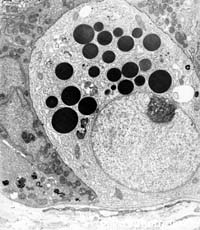

Electron microscope has been used in all areas of biological and biomedical investigations because of its ability to view the finest cell structures, and it is also used as a diagnostic tool in pathology labs for improving diagnostic and treatment of disease.

Electron microscope unit offers the tools and technical services for research and training for those who do not necessarily want to operate the electron microscope instrument, or to prepare specimen themselves. The staff of the Electron microscope unit offer training and practical services including Microscope operation, specimen preparation, digital photography and Image analysis.

New services in IMU: Electron microscpe unit offers technical services in Immunoelectron microscopy to detect the intracellular location in structures of particular proteins.